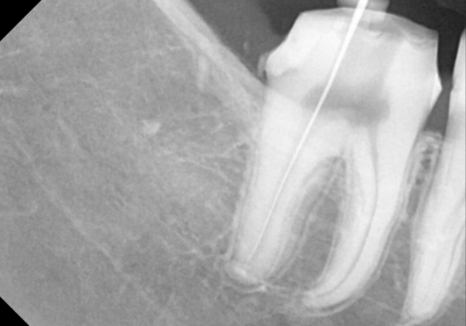

하지만 엑스레이를 찍어보니

상황이 조금 달랐습니다.

사랑니가 앞 치아(#47) 쪽으로

비스듬히 누워 있는 상태였거든요.

221231

누워 있는 사랑니라 한 번에 나오기 힘들어서,

치아를 조각낸 후 안전하게 발치를 진행했습니다.

발치는 다행히 아주 깔끔하게

마무리되었습니다.